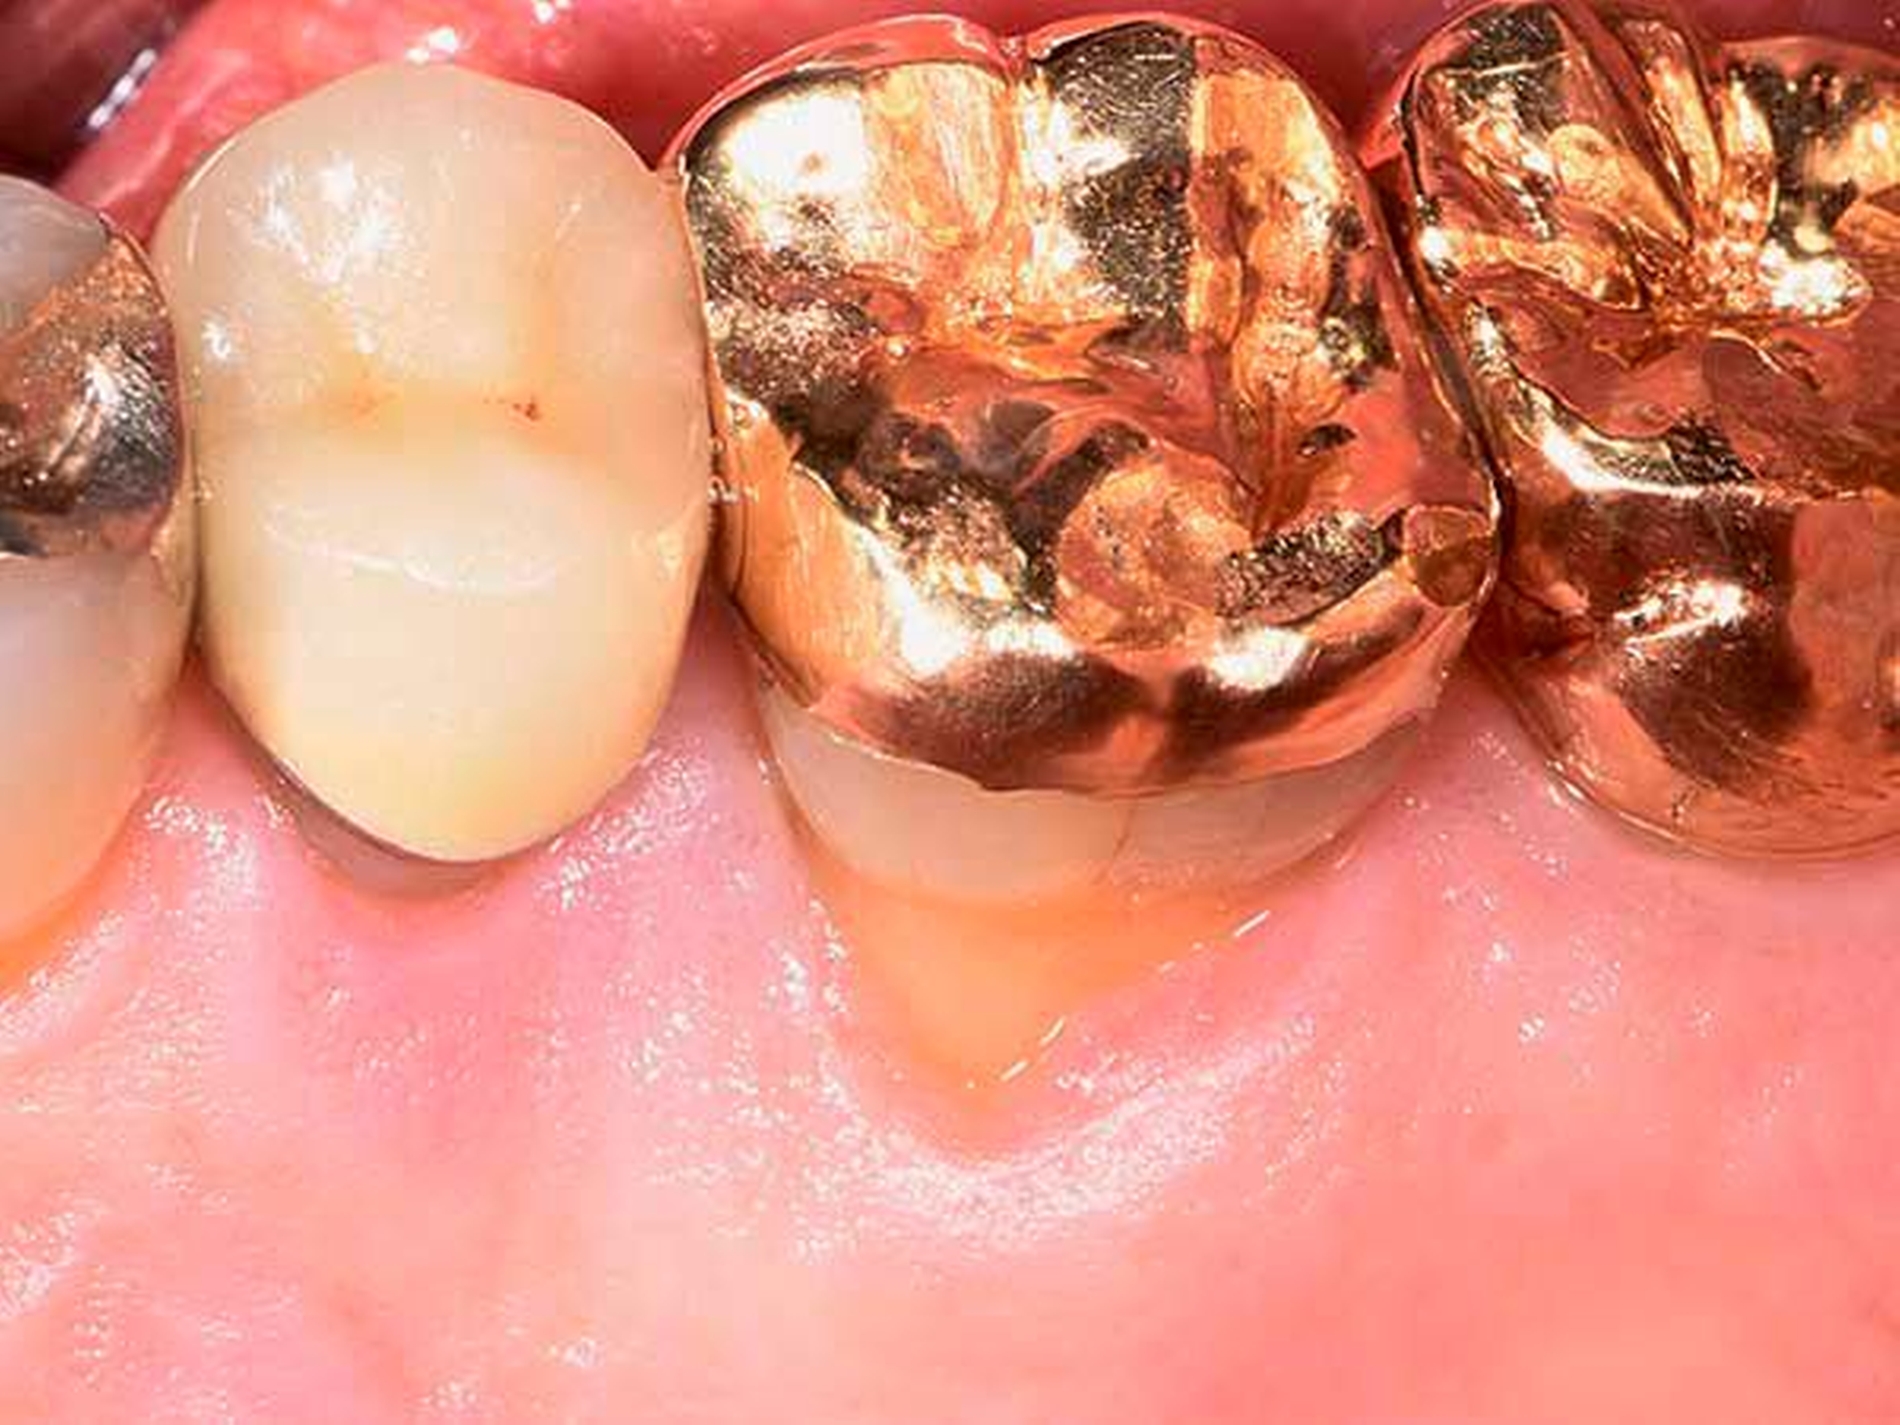

Daher gewinnen gerade im posterioren Oberkiefer oder bei Vorliegen einer durchgängigen Furkation resektive Maßnahmen wie die Amputation einer oder mehrerer Wurzeln (Abbildung 8b bis 8d), die Prämolarisierung sowie die Tunnelierung wieder an Bedeutung. Diese Maßnahmen sind klinisch herausfordernd, da neben einer hochwertigen parodontologischen Versorgung eine adäquate endodontologische Therapie und eine sinnvolle restaurative Versorgung für den Langzeiterfolg notwendig sind. Nachdem Autoren aus Italien [Carnevale et al., 1998] und den USA [Fugazzotto, 2001] schon länger von hervorragenden Überlebensraten wurzelamputierter Molaren berichtet haben, liegen nun auch aus Deutschland retrospektive Daten über bis zu 30 Jahre vor, nach denen ein Wurzel-amputierter Molar eine mediane Überlebenszeit von etwa 20 Jahren aufweist [Derks et al., 2017].

Alternativ wurde lange postuliert, Zähne mit fortgeschrittenem Furkationsbefall lieber frühzeitig zu extrahieren und durch dentale Implantate zu ersetzen. Diese sehr invasive Behandlungsoption verliert in jüngerer Zeit vor dem Hintergrund der erheblichen Inzidenz von periimplantären Erkrankungen [Derks und Tomasi, 2015], insbesondere bei Patienten mit der Vorgeschichte einer Parodontitis [Roccuzzo et al., 2014; Sousa et al., 2015], bei gleichzeitigem Fehlen von vorhersehbaren Therapiekonzepten für Periimplantitis [Renvert und Polyzois, 2015] deutlich an Bedeutung [Giannobile und Lang, 2016].